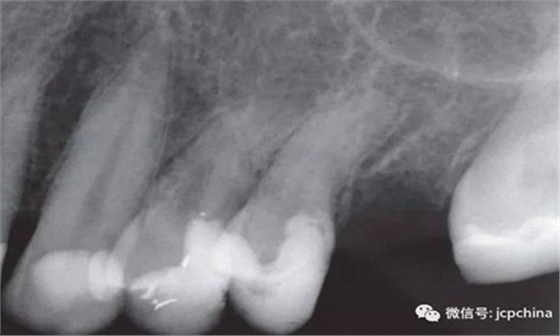

如圖所示,由于很難將圖像傳感器放置在理想的位置,造成圖像失真。當(dāng)對(duì)左上前磨牙進(jìn)行拍攝時(shí),由于淺腭穹隆的解剖結(jié)構(gòu)限制,無(wú)法進(jìn)行平行投照。